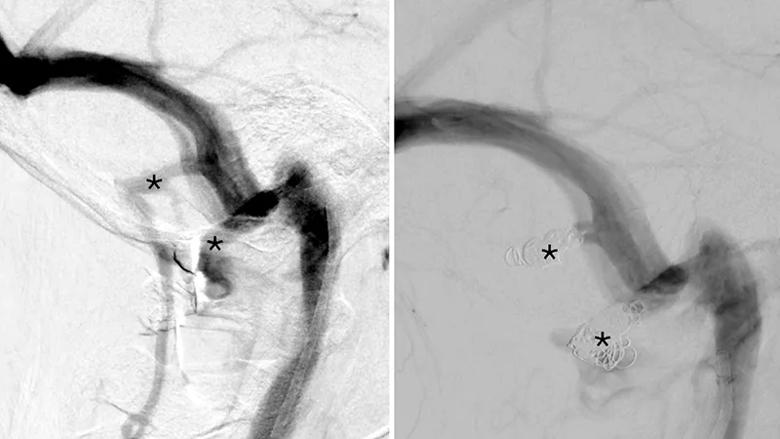

side-by-side scans of a blood vessel in the brain

Lateral digital subtraction angiograms in the venous phase show mastoid and condylar emissary veins (asterisks) before (left image) and after (right image) coil embolization in the case patient. The mastoid and condylar emissary veins provide accessory drainage from the sigmoid sinus across the skull to the paraspinal venous plexus.